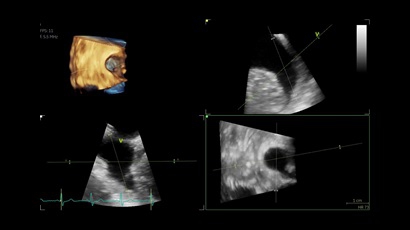

• Vivid IQ 4D с поддержкой технологии объемной реконструкции

• Передовые технологии, такие как 4D чреспищеводная эхокардиография, ЭКГ, стресс-эхо, внутрисердечная ультразвуковая эхокардиография, тканевый доплер и другие.

• Режимы: 4D, 2D (B-режим), цветной допплеровский режим, режим энергетического допплера, M-режим, цветной M-режим, спектральные режимы импульсно-волнового допплера (PW) и непрерывно-волнового допплера (CW), визуализация скорости движения тканей.

• 6VT (биплан/триплан).

• 4D AUTO AVQ - модуль автоматического выравнивания, сегментации и обсчета размеров кольца аортального клапана по объемным данным.

• 4D AUTO LVQ - модуль расчета массы миокарда ЛЖ на основе данных 4D-исследования.